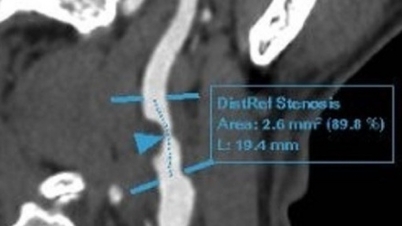

Egy férfinál 30 év dohányzás után veszélyes szív- és érrendszeri betegséget diagnosztizáltak.